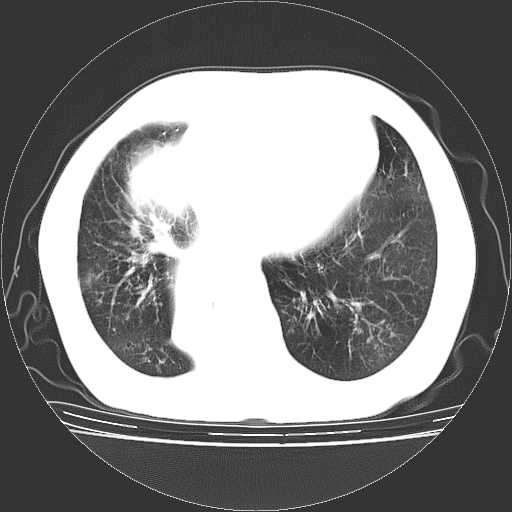

标题: CT23067:女,70岁,咳嗽、咳痰一个月,低热一周。 [打印本页]

女,70岁,咳嗽、咳痰一个月,低热一周。

1.左上肺结核,部分纤维化。右肺中下叶部分肺不张,内见液化、坏死及点状钙化,右中下叶支气管壁增厚、管腔狭窄,见多个点状钙化,结合临床考虑支气管内膜结核,建议痰检查抗酸杆菌并参考血沉。两肺多个小圆点状高密度灶,境界模糊,多考虑结核肺内播散。但本人年龄较大首先应支气管镜检以除外右肺癌。

1、右肺占位,考虑周围型ca 。

2、右下肺软组织密度肿块影,考虑肺隔离征。

3、两肺肺结核(右肺下叶背段及左肺)。